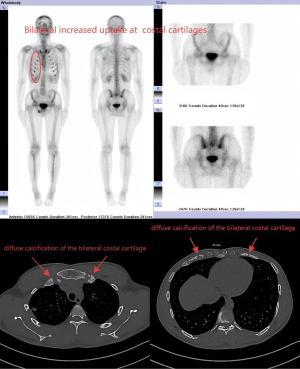

Preoperative bone scintigraphy was conducted on March 23, 2023 (Figure 1). Additionally, a CT scan at The First Affiliated Hospital of Army Medical University (Southwest Hospital) revealed areas of irregular bone density in the sternum and the anterior ends of the bilateral ribs. Findings included increased density and cortical coarsening, as well as diffuse calcification of the bilateral costal cartilage, with a markedly increased concentration of radiotracer. The diagnosis suggested abnormally active ends of the double breastbone and the anterior end of the bilateral ribs, with corresponding skeletal abnormalities of the double first anterior costal ends, and diffuse calcification of the slightly metabolically active bilateral costal cartilage. The above anomalies suggested the possibility of GH cell adenoma-related bone changes.

Postoperative bone scintigraphy was conducted on August 11, 2023 (Figure 3). The fusion images from the single-photon emission CT/CT scan revealed slightly increased metabolic activity in the sternum and the anterior ends of the bilateral ribs, along with corresponding bone abnormalities. Compared to the previous imaging, multiple calcifications of the costal cartilage were observed, along with reduced metabolic activity. These findings suggested possible bone changes associated with GH cell adenoma.

In this case, bone scintigraphy revealed distinct patterns characteristic of acromegaly, including increased metabolic activity in the sternal and the anterior ends of the bilateral ribs, as well as diffuse calcification of the costal cartilages. These findings are consistent with previous accounts of a higher prevalence of bone and joint complications in acromegaly (9,10).